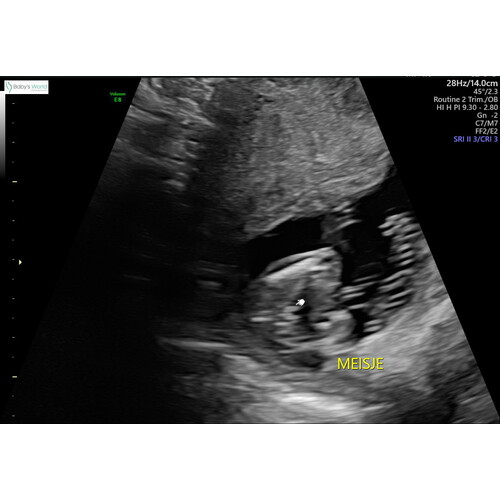

Hier de 3 streepjes bij 15 weken en 3 dagen

Ik heb ook die streepjes. Maar de nub van jen2e foto zou ik al zeggen dat jongen is🙈 maar nu weet nog niemand zeker of jullie een zoon of dochter krijgen?